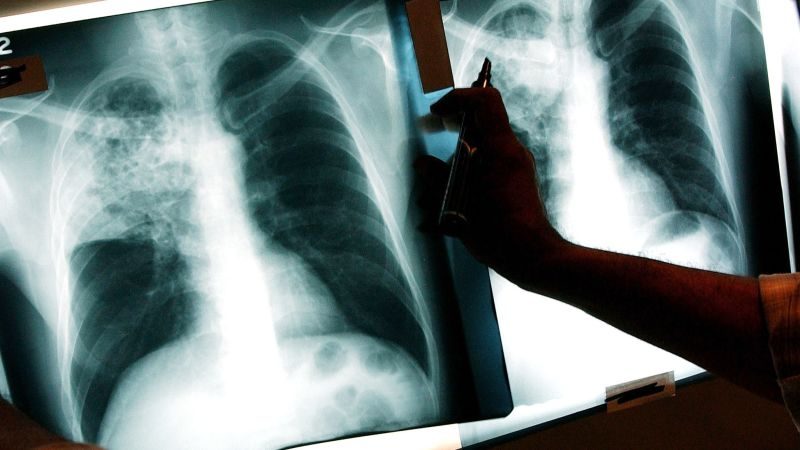

Qendra Evropiane për Kontrollin dhe Parandalimin e Sëmundjeve (ECDC) njoftoi të premten se vendet evropiane janë larg përmbushjes së objektivave të strategjisë për t’i dhënë fund tuberkulozit, duke vënë në dukje një rritje të vdekjeve prej tij në vitin 2021.

Nëse para fillimit të pandemisë COVID-19 në Evropë, incidenca dhe vdekshmëria nga tuberkulozi u ul më shpejt se në pjesën tjetër të botës, në vitin 2021 kurba e uljes së incidencës ndaloi për herë të parë në 20 vitet e fundit.

Sipas Organizatës Botërore të Shëndetësisë, referuar nga ECDC-ja, 27 mijë e 300 njerëz vdiqën nga tuberkulozi në Evropë në 2021, krahasuar me 27 mijë në vitin 2020.

“Në vitin 2021, në rajon u regjistruan më shumë se 166 mijë raste të reja dhe rikthime të tuberkulozit. Në vitin 2020 u regjistruan rreth 164 mijë raste të reja dhe rikthime të tuberkulozit, dhe në 2019 – 216 mijë”, thotë departamenti evropian.

ECDC-ja vëren se, në përgjithësi, incidenca e tuberkulozit në shumicën e vendeve evropiane është ulur gjatë pesë viteve të fundit, veçanërisht gjatë dy viteve të fundit.

Në të njëjtën kohë, “normat aktuale të rënies (incidenca) do të jenë të pamjaftueshme për të përmbushur detyrat e vendosura nga Objektivat e Zhvillimit të Qëndrueshëm të OKB-së për t’i dhënë fund epidemisë së tuberkulozit deri në vitin 2030”, thuhet në deklaratë.

Sfida të tjera që lidhen me trajtimin e tuberkulozit në rajon përfshijnë rritjen e rasteve të TB-së rezistente ndaj ilaçeve dhe përqindjet e ulëta të suksesit të trajtimit, si dhe ndërprerjet në shërbimet e TB-së për shkak të pandemisë COVID-19. /Albanianpost.com